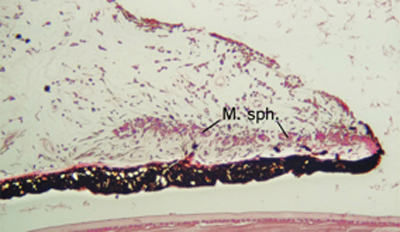

El Iris consta de fibras musculares lisas, circulares y radiales dispuestas en una estructura en forma de rosca en el estroma. El músculo Sphinter Pupillae es circumferencial y contrae la pupila con un movimiento circular, esta inervado por el 3er para craneal ( nervio Motor Ocular Común) en el que las fibras parasimpáticas partiendo del núcleo de Edinger -Westphal situado en el tronco cerebral, llegan a la pupila través de los nervios ciliares cortos; es antagonista al músculo circular-radial dilatador, Dilator pupillae, el cual hala el iris radialmente para abrir la pupila formando pliegues circulares en el estroma ciliar; es inervado por neuronas postganglionares simpáticas localizadas en el ganglio cervical superior; sus axones pasan a la rama oftálmica del Trigémino y por los nervios ciliares largos llegan al Iris. - La contracción o la dilatación en el Iris, es un reflejo fisiológico para adaptar la visión a la luminosidad del ambiente.

Cara posterior de Iris: incluye Iris y Cuerpo Ciliar, Foto tomada de globo ocular de banco de ojos.